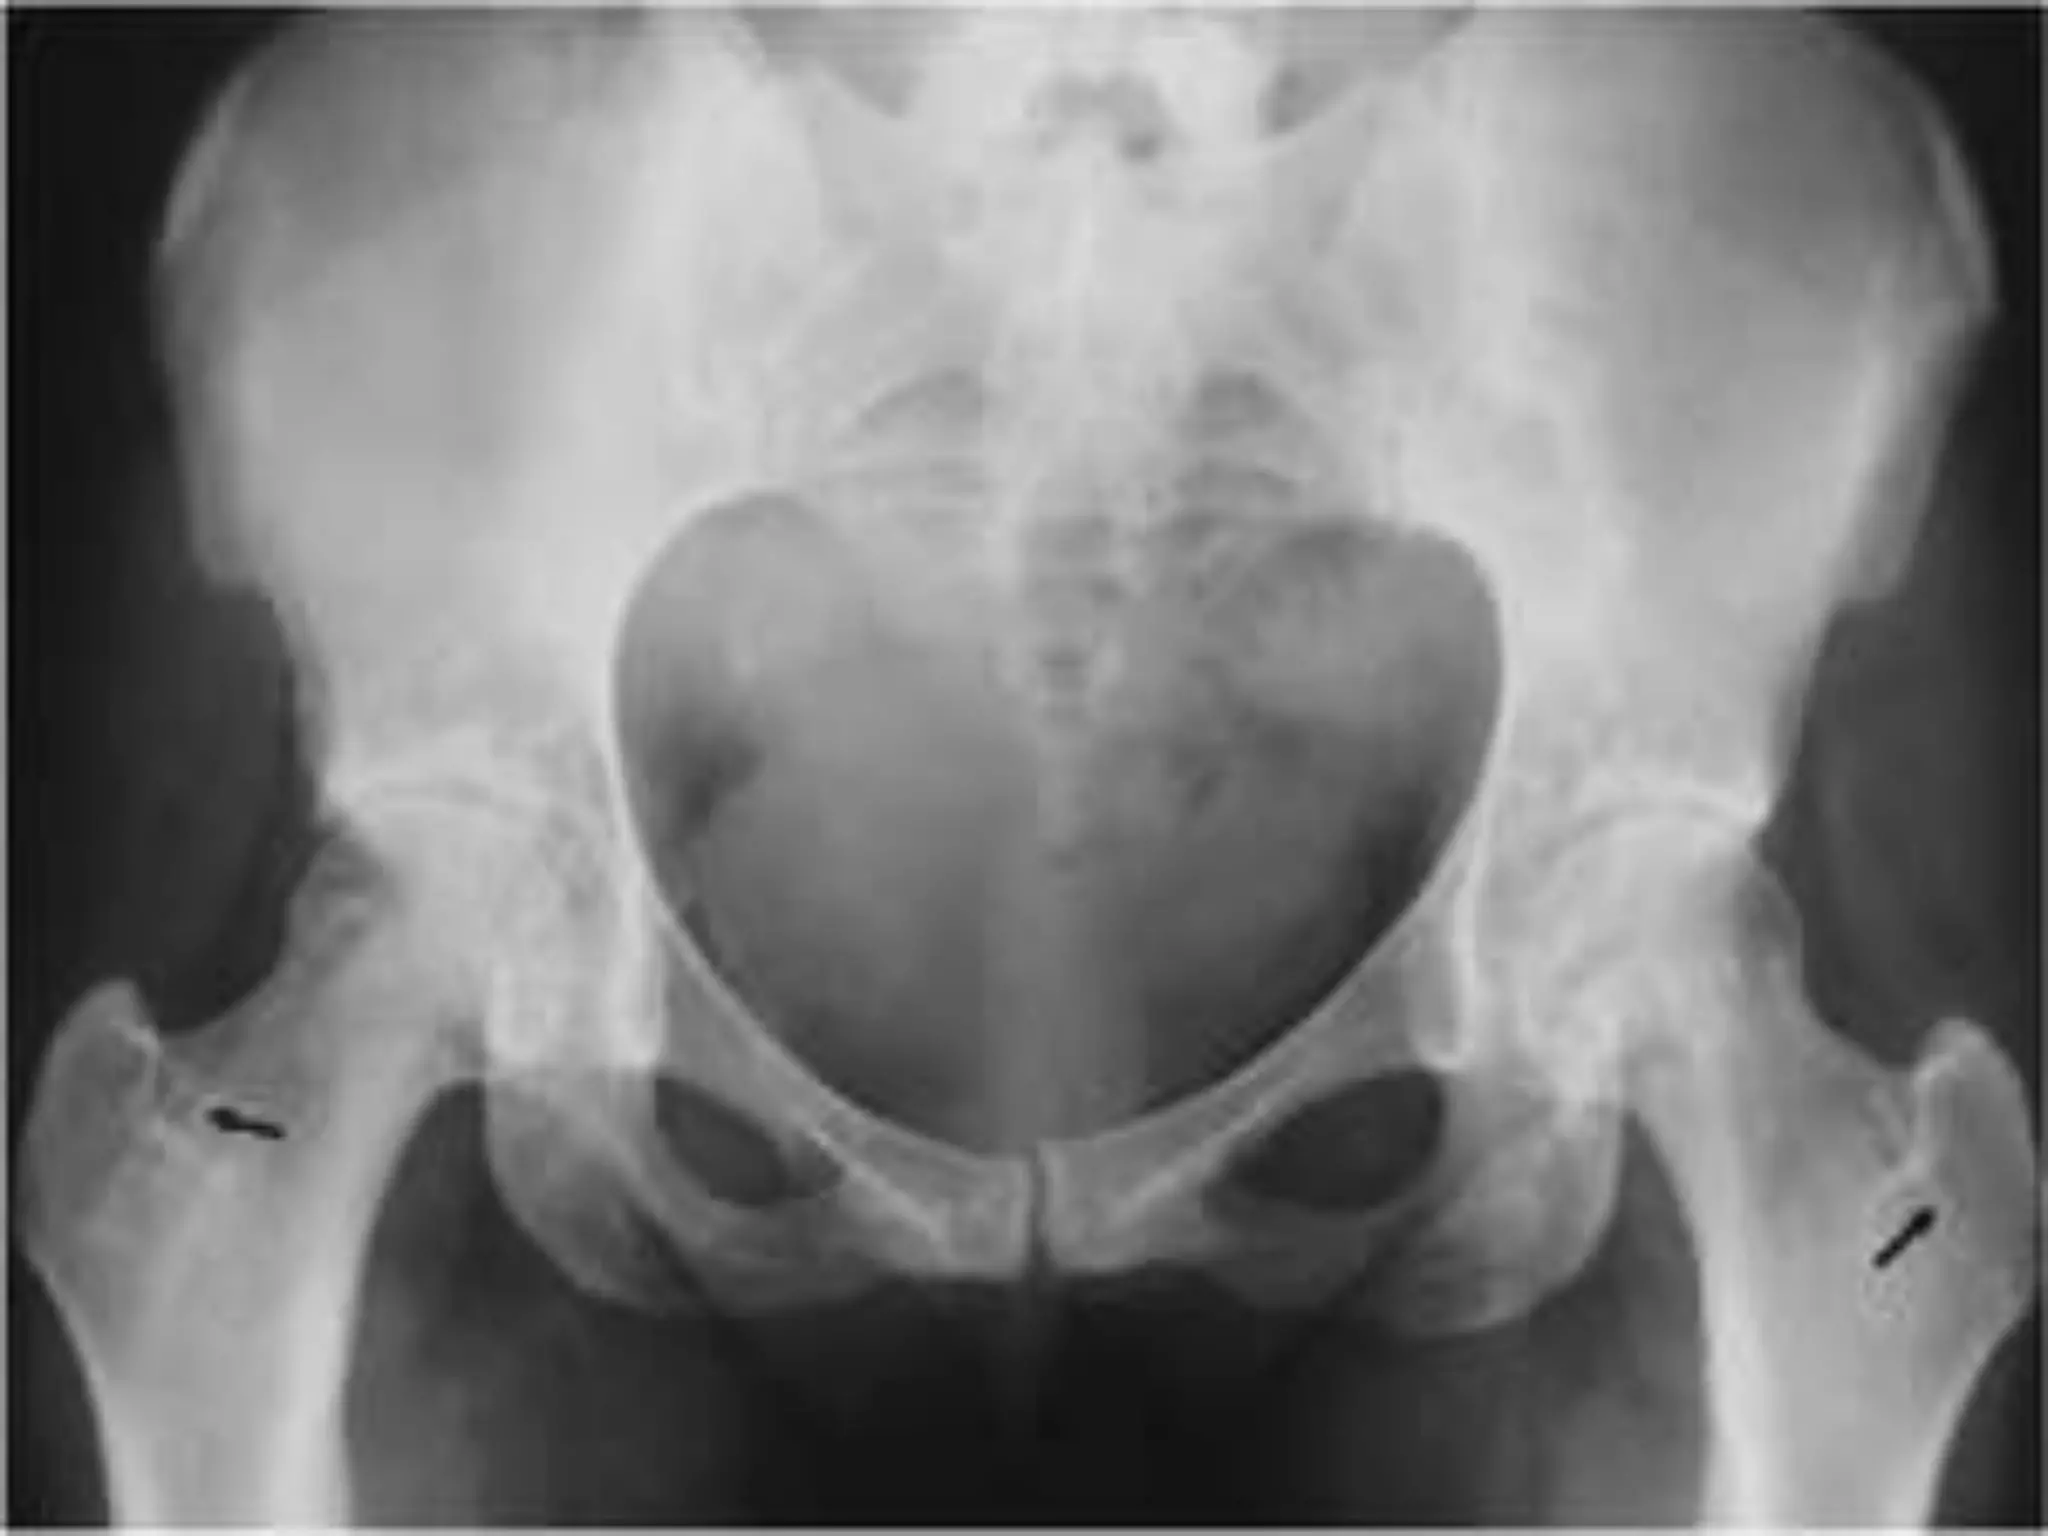

Hereditary Multiple Exostosis

Hard lumps (enlarge later) at ends of long bones and

along apophyseal borders of scapula / pelvis. (lumps

pressure on nerve/vessels).

severely affected bones become short.

Typical:

Wrist ulnar deviation, Radius bowing/subluxation,

Valgus knees/ankles

Unrestricted transverse growth of cartilagenous

physis (growth late)– Exostosis

Treatment:

Removal of exostosis.

Osteotomy for deformities .